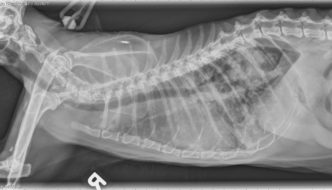

This week's case is a 15-year-old male neutered domestic short hair cat presenting for acute respiratory distress.. What is your interpretation? … [Read more...]